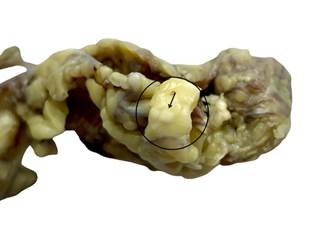

The specimen

consisted of a fibrofatty soft tissue fragment measuring 4 × 3 × 2 cm. On gross

examination, multiple discrete whitish nodules, ranging from 1 to 4 mm in

diameter, were scattered throughout the tissue (Figure 1).

Figure 1. Gross image of

peritoneal tissue showing whitish nodules (Black arrow) in the parenchyma.